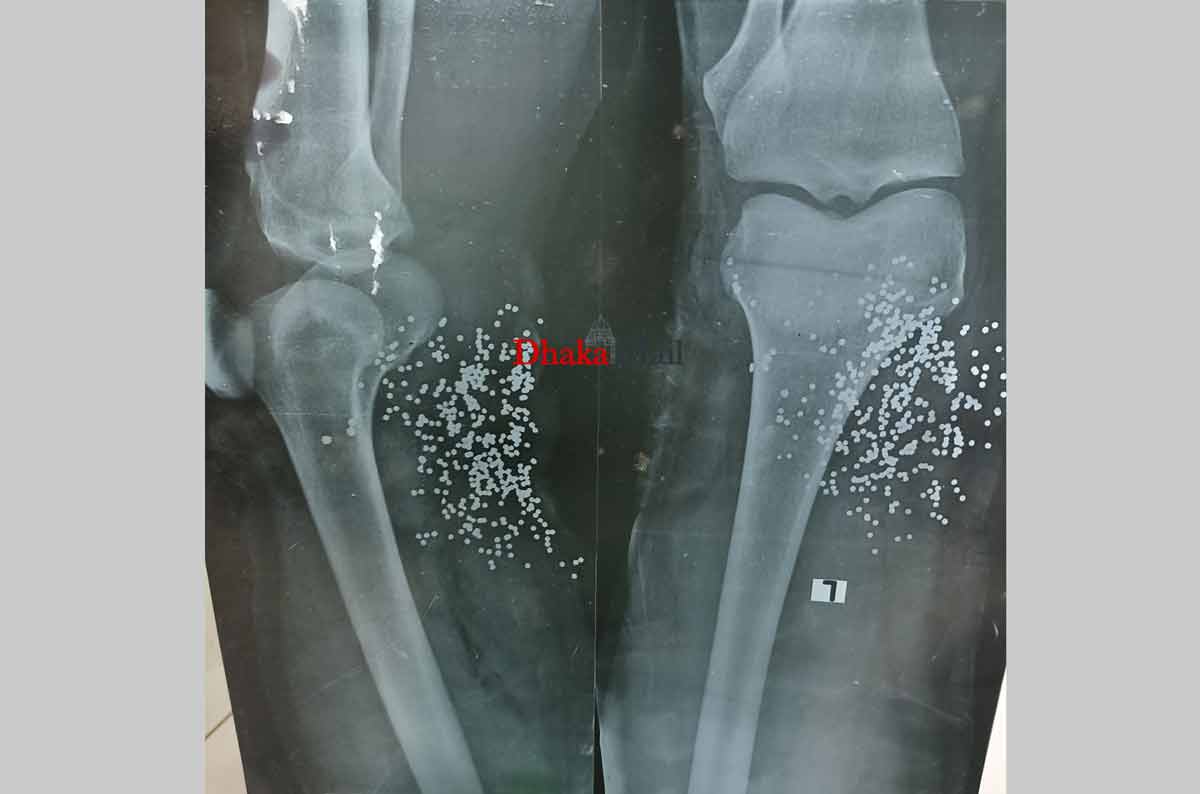

আকাশ জানান, খুব কাছ থেকে গুলি করার কারণে ছররা গুলিগুলো আশপাশে ছড়াতে পারেনি। প্রায় শতাধিক গুলি তার পায়ে লাগে। এ সময় তিনি বিছানার পাশে থাকা ব্যাগে এক্সের প্লেটটি বের করে দেখতে বলেন।

সেটি নিয়ে দেখা যায় হাটুর ঠিক নিচে গুলি করা হয়েছে। পায়ের অবস্থা এতটাই খারাপ ছিল সেটি আর রাখা যায়নি। কেটেই ফেলতে হয়েছে।